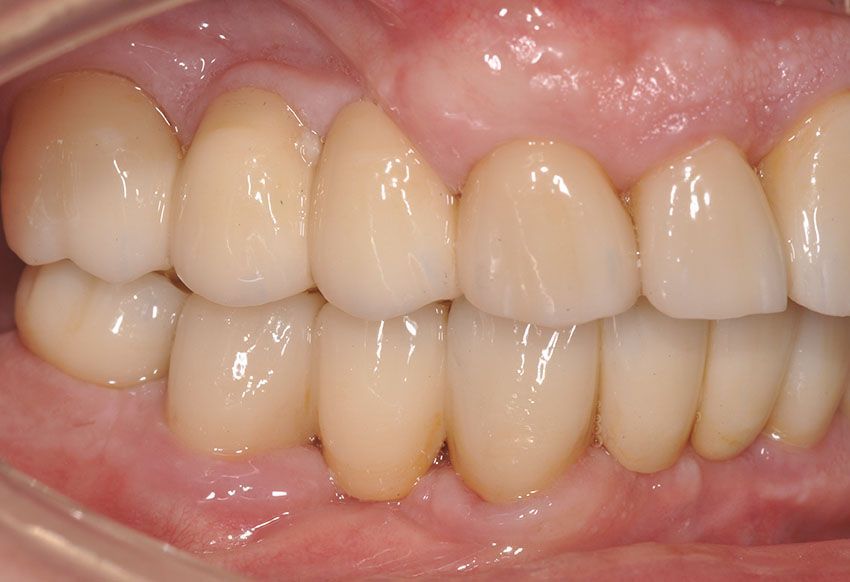

Diresti mai che è una protesi?

Il nostro obiettivo è restituire un sorriso naturale e armonioso attraverso protesi stabili ed integrate, ricorrendo alla protesi mobile solo quando non esistono alternative valide.

Ogni manufatto viene studiato sulla base delle caratteristiche del volto, del sorriso e dell’occlusione, per restituire funzionalità e comfort, esaudendo le aspettative estetiche di ogni paziente.

Le protesi fisse su impianti in particolare, offrono stabilità nel tempo, una resa estetica elevata, una sensazione naturale durante la masticazione, nonché l'integrazione ottimale con denti e tessuti. Il paziente viene accompagnato in ogni fase, dalla pianificazione alla finalizzazione del lavoro, con

pazienza, trasparenza e professionalità.